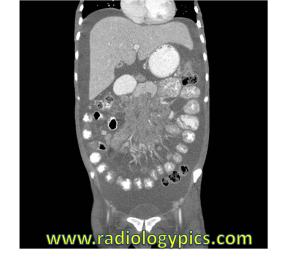

History: 30 year old female with HIV and abdominal pain.

What is your differential diagnosis given the findings in this 30 year old female with a history of HIV and abdominal pain?